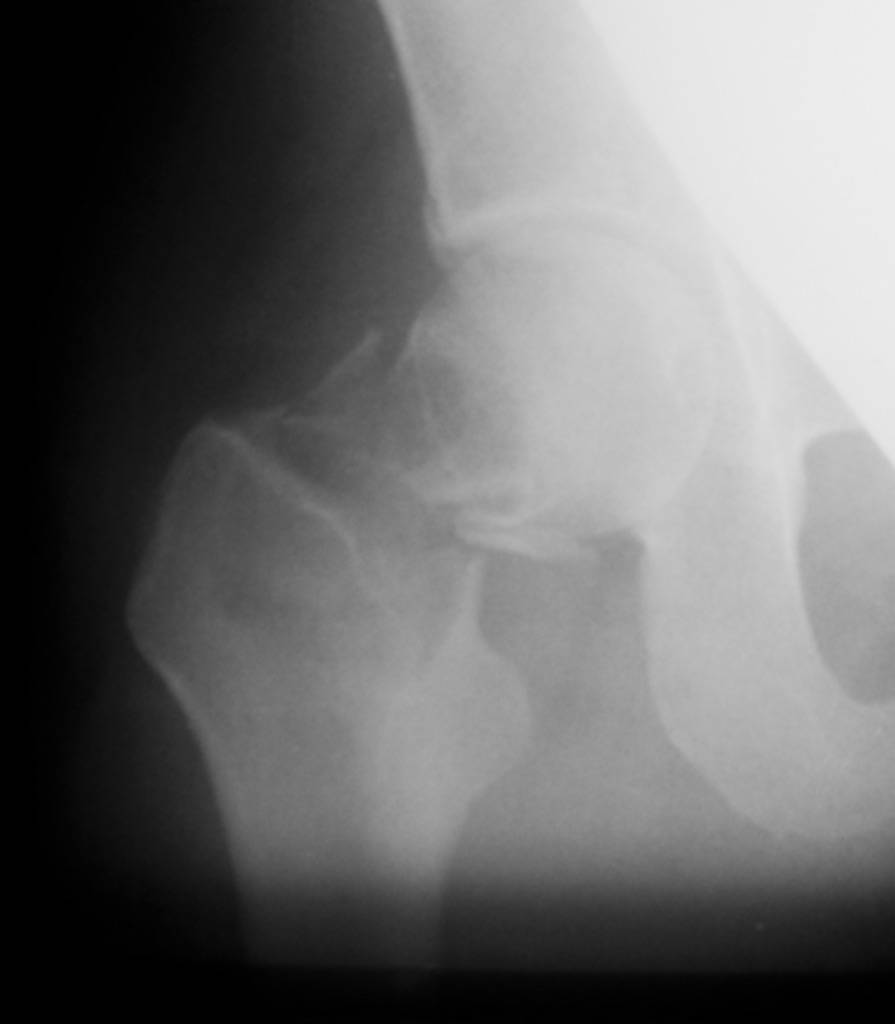

Приношу извинения, думал, что на прилагающейся рентгенограмме видно, что перелом произошел на месте обширной кисты, занимающей шейку и вертельную область. По характеру перелом многооскольчатый, дуга Адамса также представлена в виде осколков.

Если нет подозрений на первичную злокачественую опухоль, тогда опять остеосинтез, но конструкцией с угловой стабильностью, т.е. либо гамма/PFN (я бы выбрал), либо DHS. Без пластики. Вероятно, КТ могла

бы уточнить протяженность. Но головка выглядит хорошо, есть за что зацепиться.